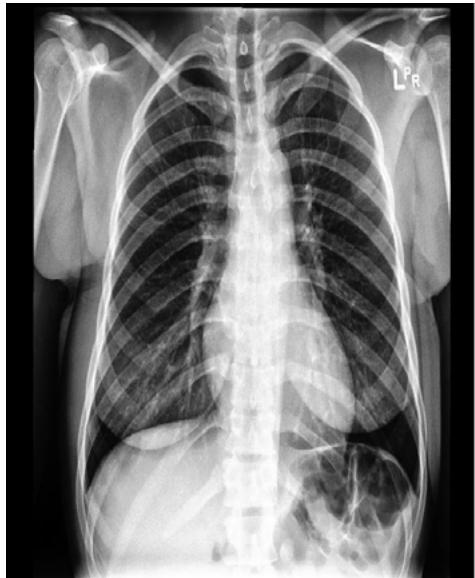

A: Frontal View

B: Lateral View Figure 2: Views of CXR in CheXpert Dataset (Source: Irvin et al, 2019).